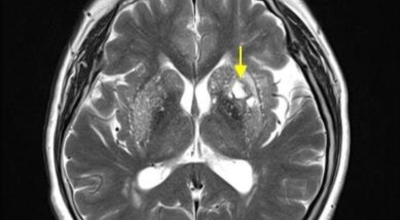

뇌조직은 평소에도 다량의 혈류를 공급받고 있는데 어떤 여러가지 원인으로 인해서 뇌혈관에 이루는 관이 막히는 경우 뇌에 공급되는 혈액량이 떨어지면서 뇌조직이 기능을 제대로 하지 못하게 되는데 이렇게 뇌혈류 감소가 일정 시간 이상 지속되다 보면 뇌조직의 괴사가 시작되어 회복 불가능한 상태가 되는데 이를 뇌경색이라 해요. 오늘 알아볼 질병은 뇌경색 초기증상이예요.

뇌경색의 경색이란 허혈성 괴사를 말해요. 여기서 허혈이란 혈관이 막히는 것을 말하고 괴사는 말 그대로 일부가 죽는 것을 말하는데 뇌경색의 경우 뇌의 혈관이 막혀 뇌세포 일부가 죽는 걸 의미해요. 뇌혈관이 막혔다 해서 혈액 공급이 안되는것은 또 아니에요.

막힌 혈관으로도 혈액이 공급되긴 하나 혈관이 막혀있어 혈액을 보내긴 하나 제대로 흐르지 못하고 혈액이 쌓이고 축적되어 물풍선에 물이 꽉 차서 터지듯 뇌혈관이 터지는 경우가 일어날 수 있는데 이를 뇌출혈 이라고 해요. 물론 외상으로 인한 뇌출혈도 있지만 이처럼 뇌경색으로 인해 혈관이 막혀 터지는 경우도 있어요.